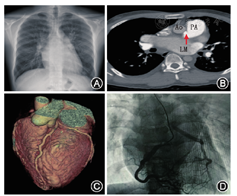

入院查体:体温36.5 ℃,心率71次/min,呼吸23次/min,血压90/60 mmHg。发育正常,浅表淋巴结无肿大。双肺未闻及啰音及胸膜摩擦音。心律齐,心尖部可闻及粗糙的3/6级全收缩期杂音,向左腋下传导,P2>A2。肝脾未触及,下肢不肿。入院后针对肺动脉高压病因进行筛查,动脉血气分析(未吸氧):pH 7.415,pCO2 31 mmHg,pO2 89.3 mmHg,SaO2 96.6%。血常规、尿粪常规、肝肾功能未见明显异常。NT-proBNP 778.5 pg/ml。C反应蛋白、类风湿因子、免疫球蛋白、补体、血沉、抗核抗体谱、狼疮抗凝物、抗心磷脂抗体、抗血管炎抗体、甲状腺功能、D二聚体及凝血因子活性均处正常范围。胸部X线(图1A):双肺门动脉扩张,外周肺纹理相对纤细,肺动脉段饱满,左房室增大,心胸比0.49。睡眠呼吸监测:不符合睡眠呼吸暂停综合征。下肢静脉超声未见明显异常。核素肺通气灌注显像:双肺血流不均匀受损,符合肺动脉高压改变。超声心动图:左房前后径52 mm,左室舒张末径51 mm,左室射血分数62%,右室前后径22 mm,估测肺动脉收缩压80 mmHg;二尖瓣脱垂并大量反流,左冠状动脉似起源于右肺动脉。因超声心动图提示患者可疑左冠状动脉异常起源,我们进一步行肺动脉CTA检查证实(图1B、图1C):冠状动脉左主干异常起源于主肺动脉右侧壁;肺动脉段以上分支未见栓塞征象。同时,完善冠状动脉造影(图1D):右冠状动脉起源于右冠窦,右、左冠状动脉之间可见丰富侧支循环,左冠状动脉逆向显影。我院右心导管检查:肺动脉压74/31/45 mmHg,肺小动脉楔压28 mmHg,肺血管阻力4.3 Wood,心指数2.54 L·min-1·m-2。至此,患者最终诊断:先天性心脏病,左冠状动脉起源肺动脉,二尖瓣脱垂,左心扩大,阵发性心房颤动,肺动脉高压。患者为毛细血管后性肺动脉高压,给予利尿剂对症治疗。同时请心外科会诊,考虑患者冠状动脉起源异常,有活动后胸闷、晕厥症状,并发二尖瓣重度关闭不全,存在心外科手术指征,择期于2019年4月21日行冠状动脉起源异常矫正及二尖瓣成形术。患者术后恢复好,术后第4天复查超声心动图:左房前后径:30 mm,左室舒张末径48 mm,左室射血分数60%,估测肺动脉收缩压54 mmHg。随访至2019年9月,患者病情稳定,活动耐量增加,未再发作晕厥。